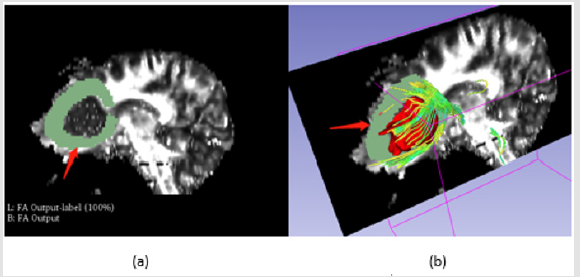

Fibers Segmentation in Sagittal Section: Considering the direction of the fibers, the peritumoral region should include those in left-right direction which could be displayed in sagittal section, (Figure 4) shows the labeling process on sagittal section.

Figure 4: Fibers segmentation in sagittal section, a is manual label around the tumor as red arrow shows, b is the visualization of fibers.